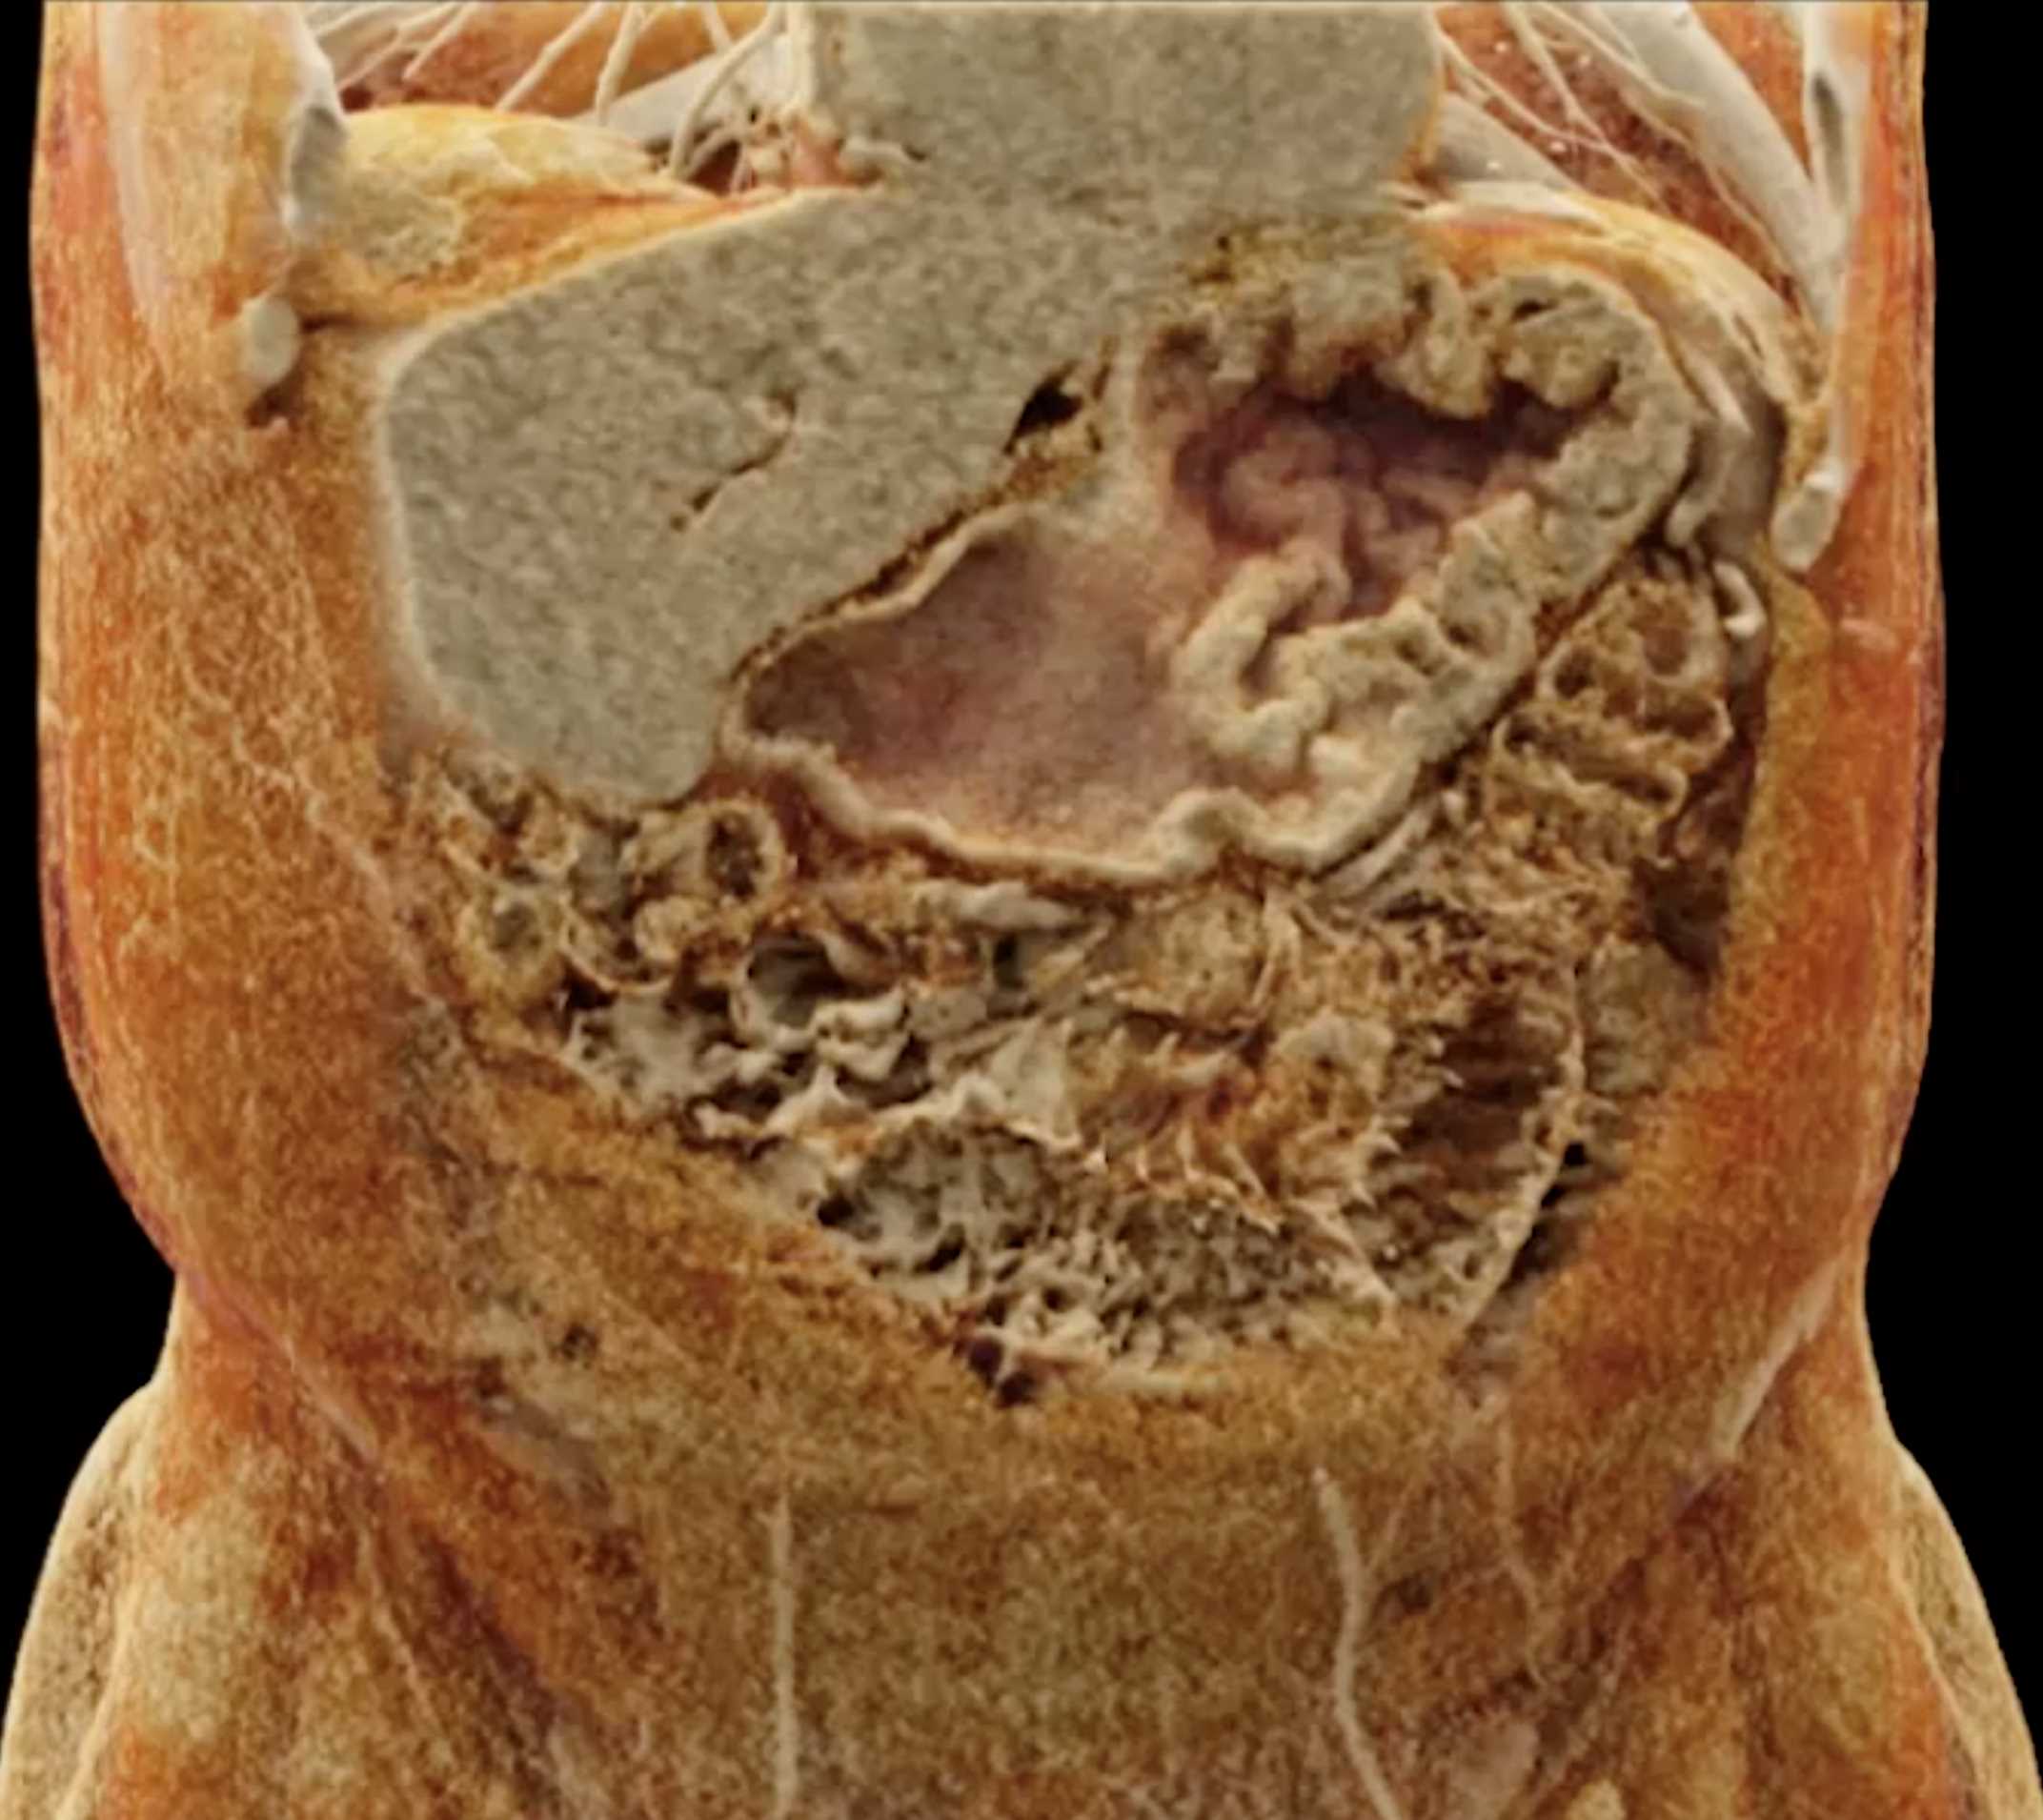

Chemical Gastritis due to NSAIDs